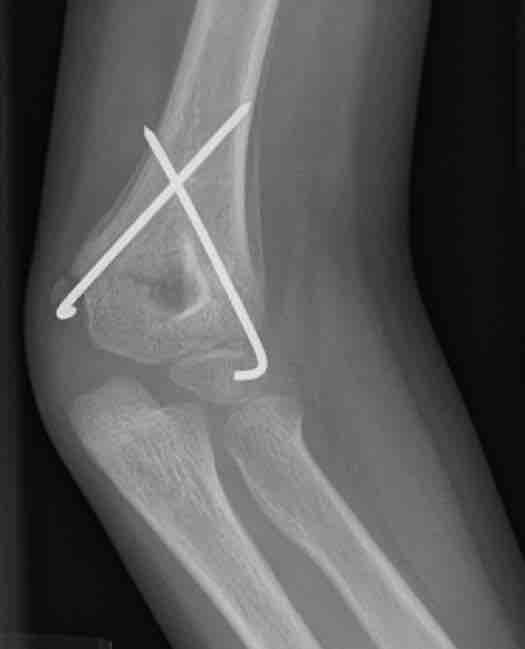

This figure depicts a radiograph of a child's healing supracondylar humeral fracture that has been treated with closed reduction and pinning. This image, taken three weeks post injury, demonstrates the benign periosteal reaction of normal healing bone.

This is a radiographic image (x-ray) of a child's healing supracondylar humeral fracture that has been treated with closed reduction and pinning. This image, taken three weeks post injury, demonstrates the benign periosteal reaction of normal healing bone.